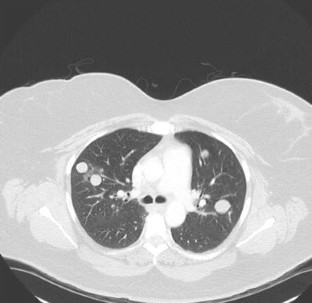

Benign Metastasizing Leiomyomas Following Myomectomy and Uterine Artery Embolization

Benign metastasizing leiomyomas (BMLs) are rare sequelae of common uterine leiomyomas and most frequently found in the lungs. Most cases of BMLs occur with a history of prior gynecologic procedures; however, none have yet been reported in association with uterine artery embolization (UAE). This case report highlights the disease course for a 48-yo female with a history of both myomectomy and UAE for uterine fibroids who presented later with bilateral pulmonary BMLs. Though the pathophysiology of BMLs is poorly understood and this case is confounded by prior myomectomy, it does bring into question whether UAE has a role in BML development. Regardless, UAEs have become a routine procedure and interventionalists should be aware of the possibility of BMLs in post-fibroid treatment patient populations.

Fig. 3

• Uterine fibroid embolization

• Benign metastasizing leiomyoma

• Pulmonary nodules